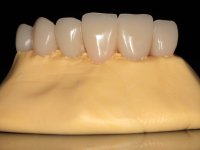

The working model was scanned and the dental technician developed a zirconia framework based on the diagnostic wax-up. This framework try-in was done, the perfect fit was assessed, and a final impression was done with a light silicone.

The bridge was finally placed with a progressive screwing to allow the tissue to accommodate the pressure of the pontics and the abutments emergency profiles.